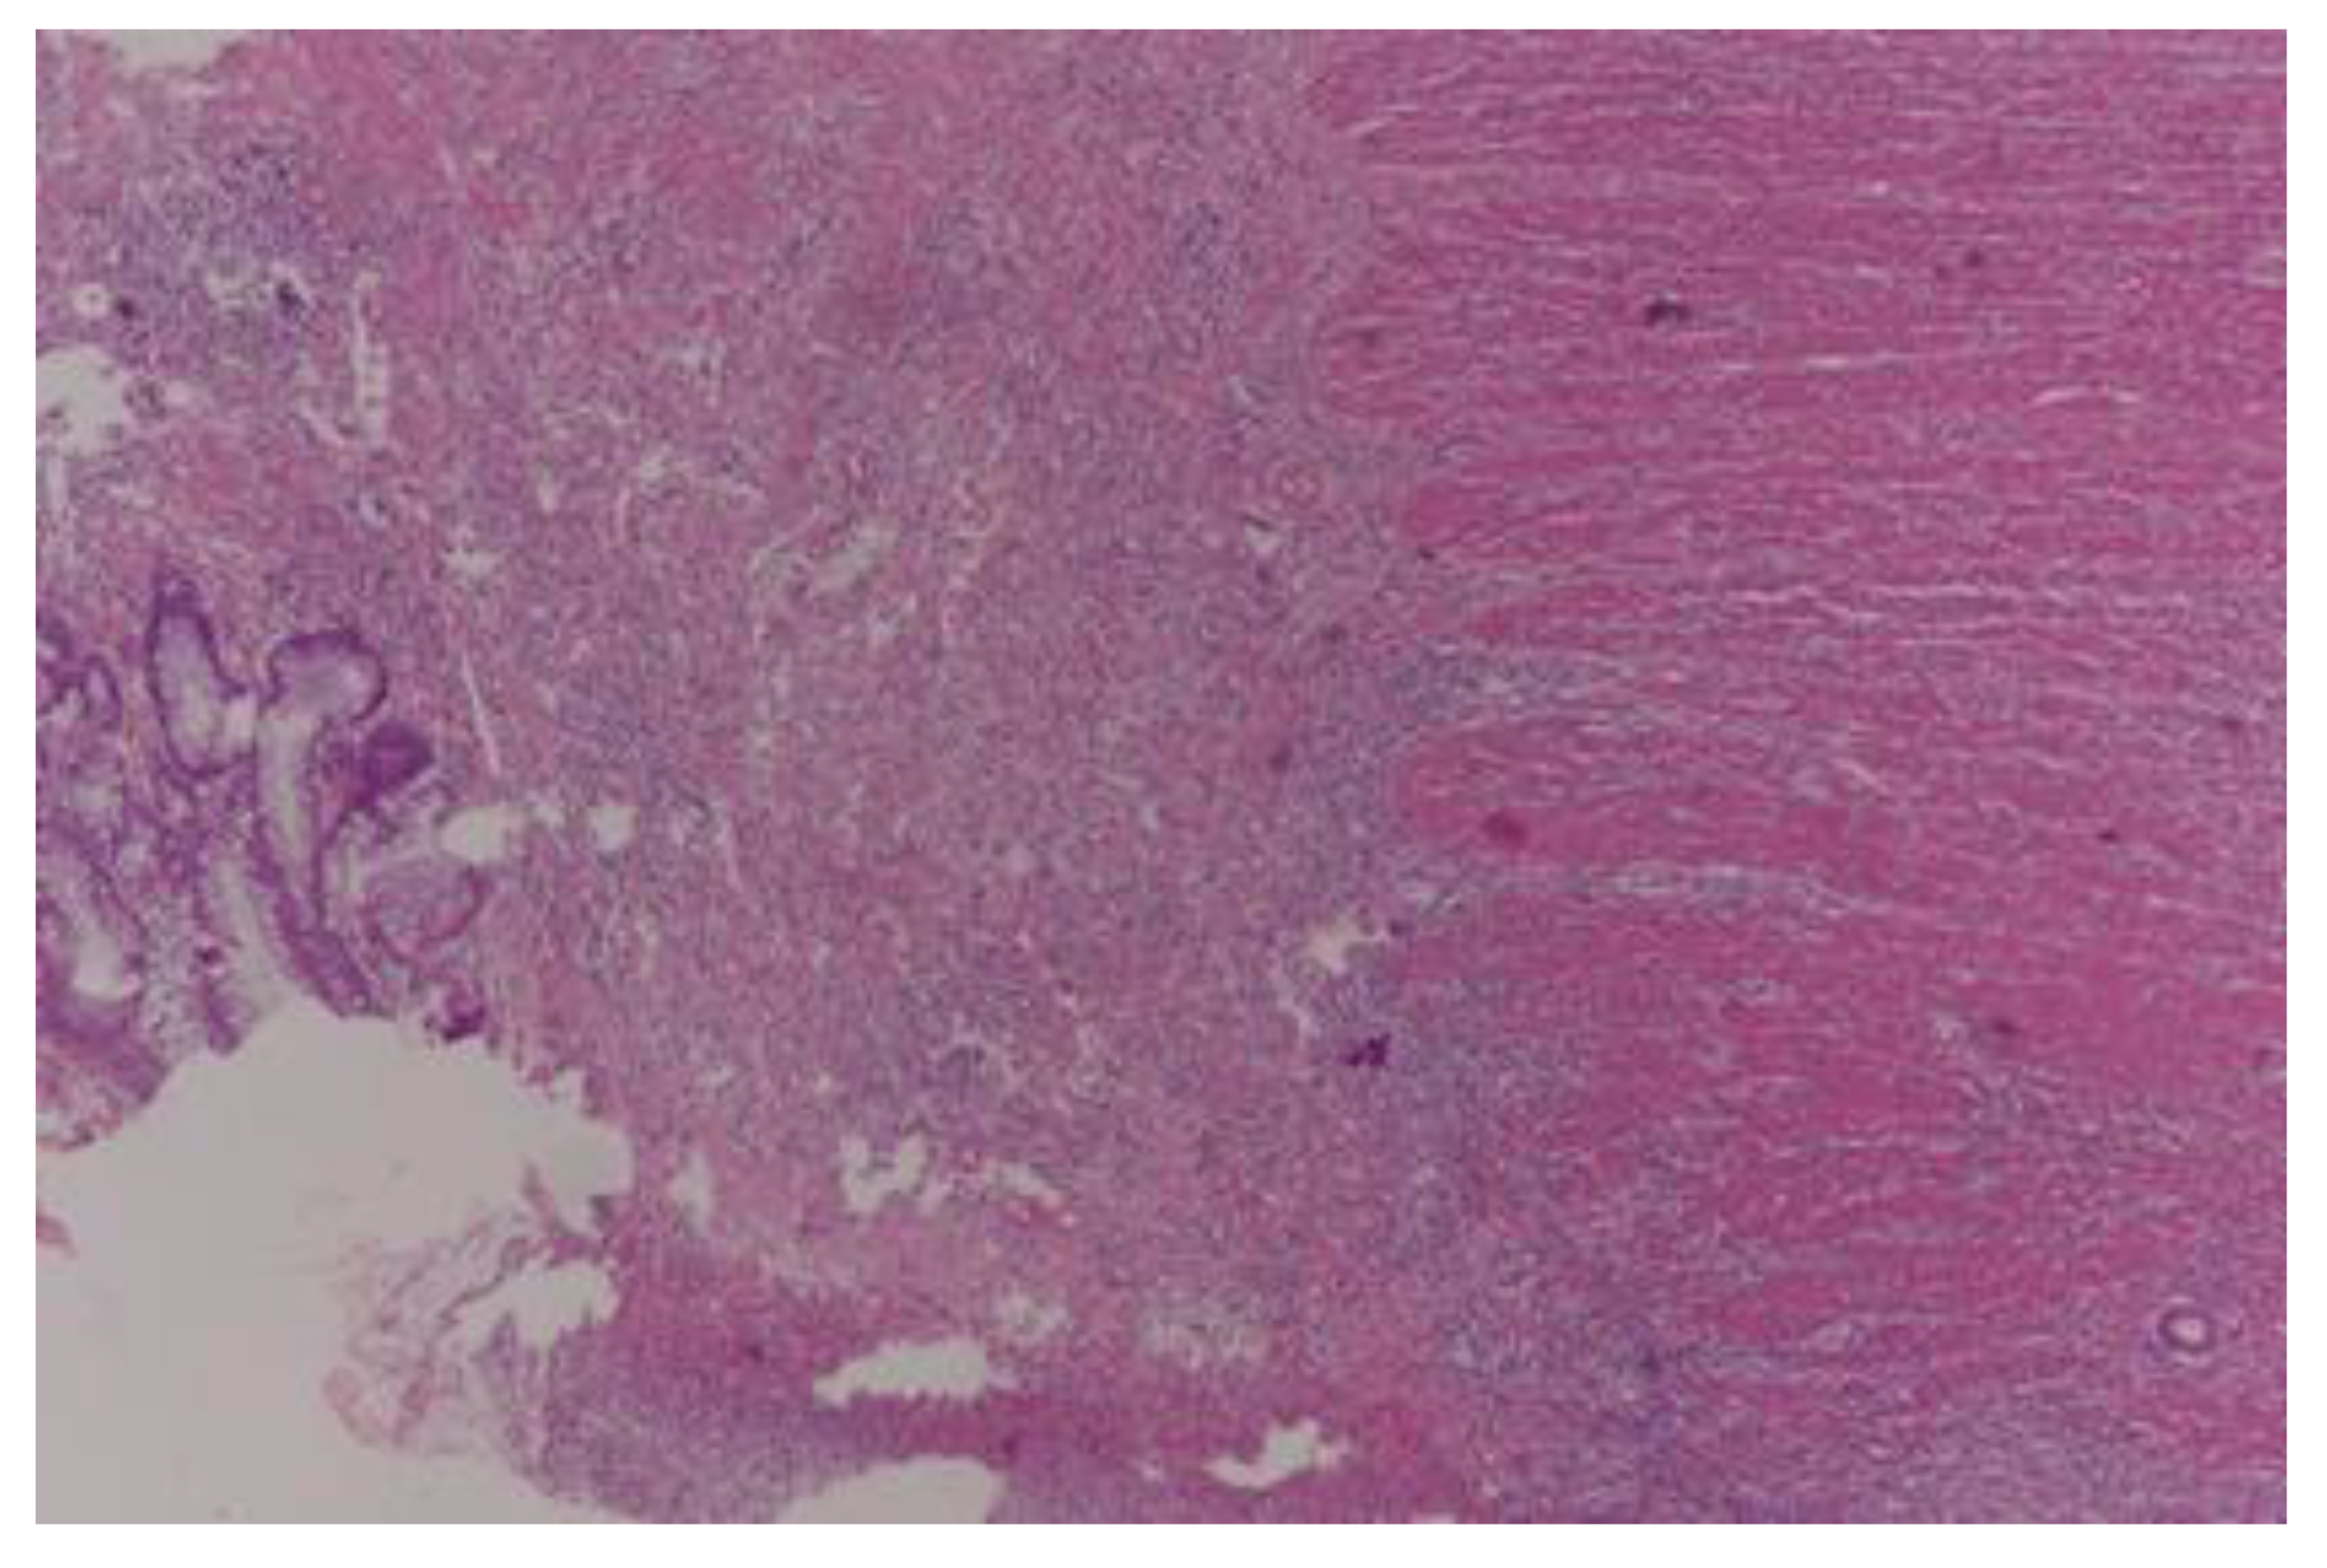

- Dworak, O.; Keilholz, L.; Hoffmann, A. Pathological features of rectal cancer after preoperative radiochemotherapy. Int. J. Color. Dis. 1997, 12, 19–23. [Google Scholar] [CrossRef] [PubMed]

- Ryan, R.; Gibbons, D.; Hyland, J.M.; Treanor, D.; White, A.; Mulcahy, H.E.; O’Donoghue, D.P.; Moriarty, M.; Fennelly, D.; Sheahan, K. Pathological response following long-course neoadjuvant chemoradiotherapy for locally advanced rectal cancer. Histopathology 2005, 47, 141–146. [Google Scholar] [CrossRef]

- Chen, H.Y.; Feng, L.L.; Li, M.; Ju, H.Q.; Ding, Y.; Lan, M.; Song, S.M.; Han, W.D.; Yu, L.; Wei, M.B.; et al. College of American Pathologists Tumor Regression Grading System for Long-Term Outcome in Patients with Locally Advanced Rectal Cancer. Oncologist 2021, 26, e780–e793. [Google Scholar] [CrossRef] [PubMed]